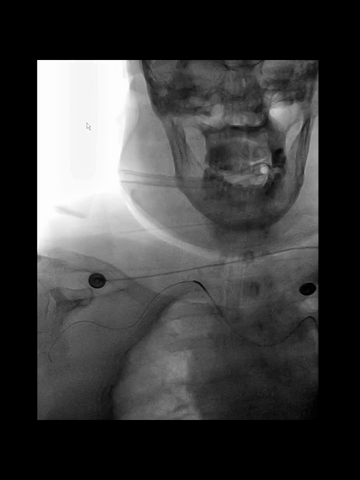

穿刺右桡动脉,置入6F桡鞘;4F长多功能管(125cm)和Navien 072(105cm)组成同轴,泥鳅导丝导引下,4F管头端行至右锁骨下动脉近端。

经4F管送入先前的微导管微导丝,微导丝顺利通过右V1曲折,跟进微导管过程中,支撑不足,弹回右锁骨下动脉。

调整4F头端位置和方向,经数次尝试后,微导丝再次进入右椎动脉,并克服V1曲折上高到V3。

后续微导管顺利跟进到V3,撤出Command 14导丝,送入0.18"导丝(Commmand 18)导丝增强支撑,此时中间管沿微导管微导丝推送到V3。

中间管被进一步推高到V4近端。

3、根据术前急诊CTA结果,左椎动脉颅内段显影不清,故决定经右椎动脉入路。

4、术前CTA示弓形和弓上血管情况,预测经股穿刺治疗难度不大;出乎所料的是,因右锁骨下动脉迂曲和右椎动脉V1曲折,导致经股路径建立通道难度大,经改变策略尝试失败后,为节约时间,故果断改经桡穿刺。